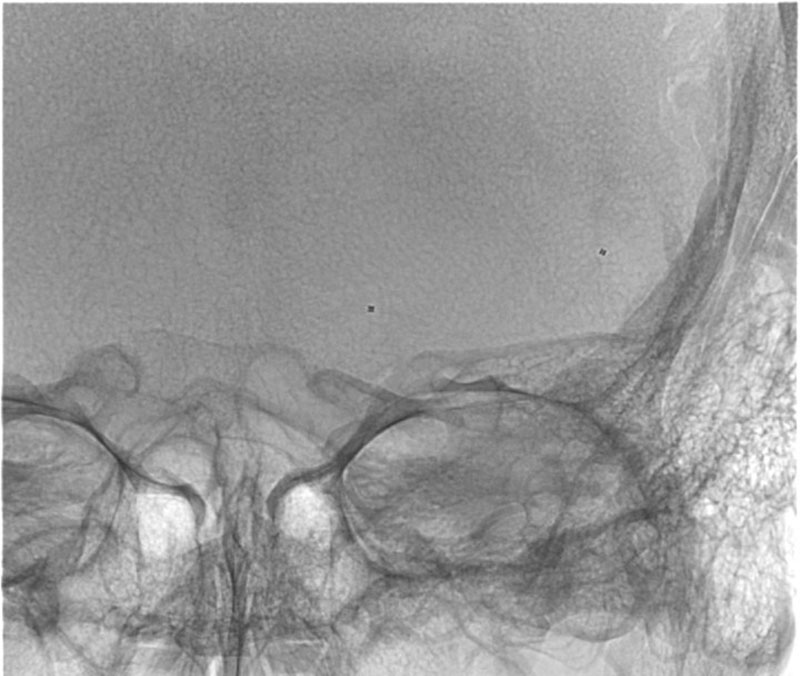

DSA

L - VERT

L - ICA

VASO-CT post